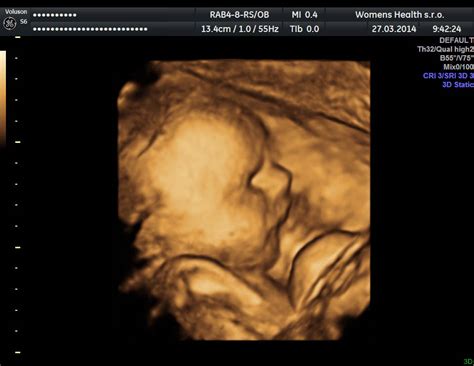

4D ultrazvuk je technológia, pri ktorej sa bábätko zobrazuje v trojrozmernom obraze v reálnom čase (3D značí trojrozmernosť obrazu a štvrtá jednotka predstavuje čas). Na vyšetrení teda môžeš vidieť aktuálne pohyby dieťaťa a jeho mimiku. Na rozdiel od 2D ultrazvuku, ktorým je vykonávaná väčšina ultrazvukov v tehotenstve, 4D ultrazvuk poskytne omnoho plastickejší pohľad, dôsledkom čoho je táto metóda využívaná aj v prenatálnej diagnostike. Najviac sa v rámci diagnostiky dieťatka 4D zobrazenie používa pri vyšetrení srdiečka a jeho funkcie.

3D ultrazvuk predstavuje ultrasonografickú metódu zobrazovania plodu alebo jeho štruktúr trojrozmerným spôsobom. Skratka „3D“ znamená „trojrozmerné (trojdimenzionálne)“ zobrazovanie. 4D ultrazvuk, na rozdiel od 3D ultrazvuku, predstavuje trojrozmerné zobrazovanie v reálnom čase. „Štvrté D“ v skratke „4D“ je „čas“. 3D/4D ultrazvuk sa môže vykonať kedykoľvek počas tehotenstva a môže byť doplnkom konvenčného 2D (dvojrozmerného) ultrazvuku.

Kto by nechcel mať na tehotenstvo peknú spomienku? Hoci ide o obdobie, ktoré nastávajúcu maminku dokáže aj celkom potrápiť, na ten pocit, keď pod srdcom nosila vytúženého drobčeka, nechce zabudnúť nikdy. Jednou z možností, ako si pamiatku na obdobie s bruškom zvečniť, je aj absolvovanie 3D ultrazvuku. Vďaka 3D ultrazvuku budeš mať fotografiu bábätka, najčastejšie sa zobrazuje jeho tvárička, ktorá už na začiatku tretieho trimestra má presne tie tvárové črty, aké bude mať bábätko aj po narodení. Na 4D ultrazvuku môžeš pozorovať bábätko v reálnom čase a pozerať sa, ako sa práve pohybuje, mračí, usmieva alebo hýbe ručičkami. Domov si odnesieš video záznam na USB kľúči. Lekár vám môže aj vytlačiť 3D fotografiu dieťatka.